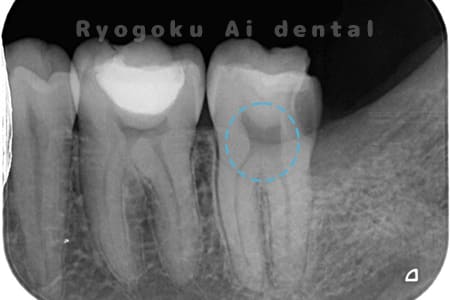

Case08

-

- 原因

- 重度カリエス

- 治療内容

- 断髄治療

- 治療回数

- 1回

- 治療費用

- 66,000円

右下に違和感があるとのこでご来院。レントゲンでも神経に達する虫歯があり、神経の保存を行う断髄治療について説明し、同意を得て行いました。特に知覚過敏症状もなく、神経の反応も良好なため、今後は定期検診にて経過を追っていくこととなりました。

<リスク・副作用>

術後は痛み、腫れ、痺れなどの副作用が生じる場合があります。症状が再発する可能性があります。その場合は抜髄する必要があります。